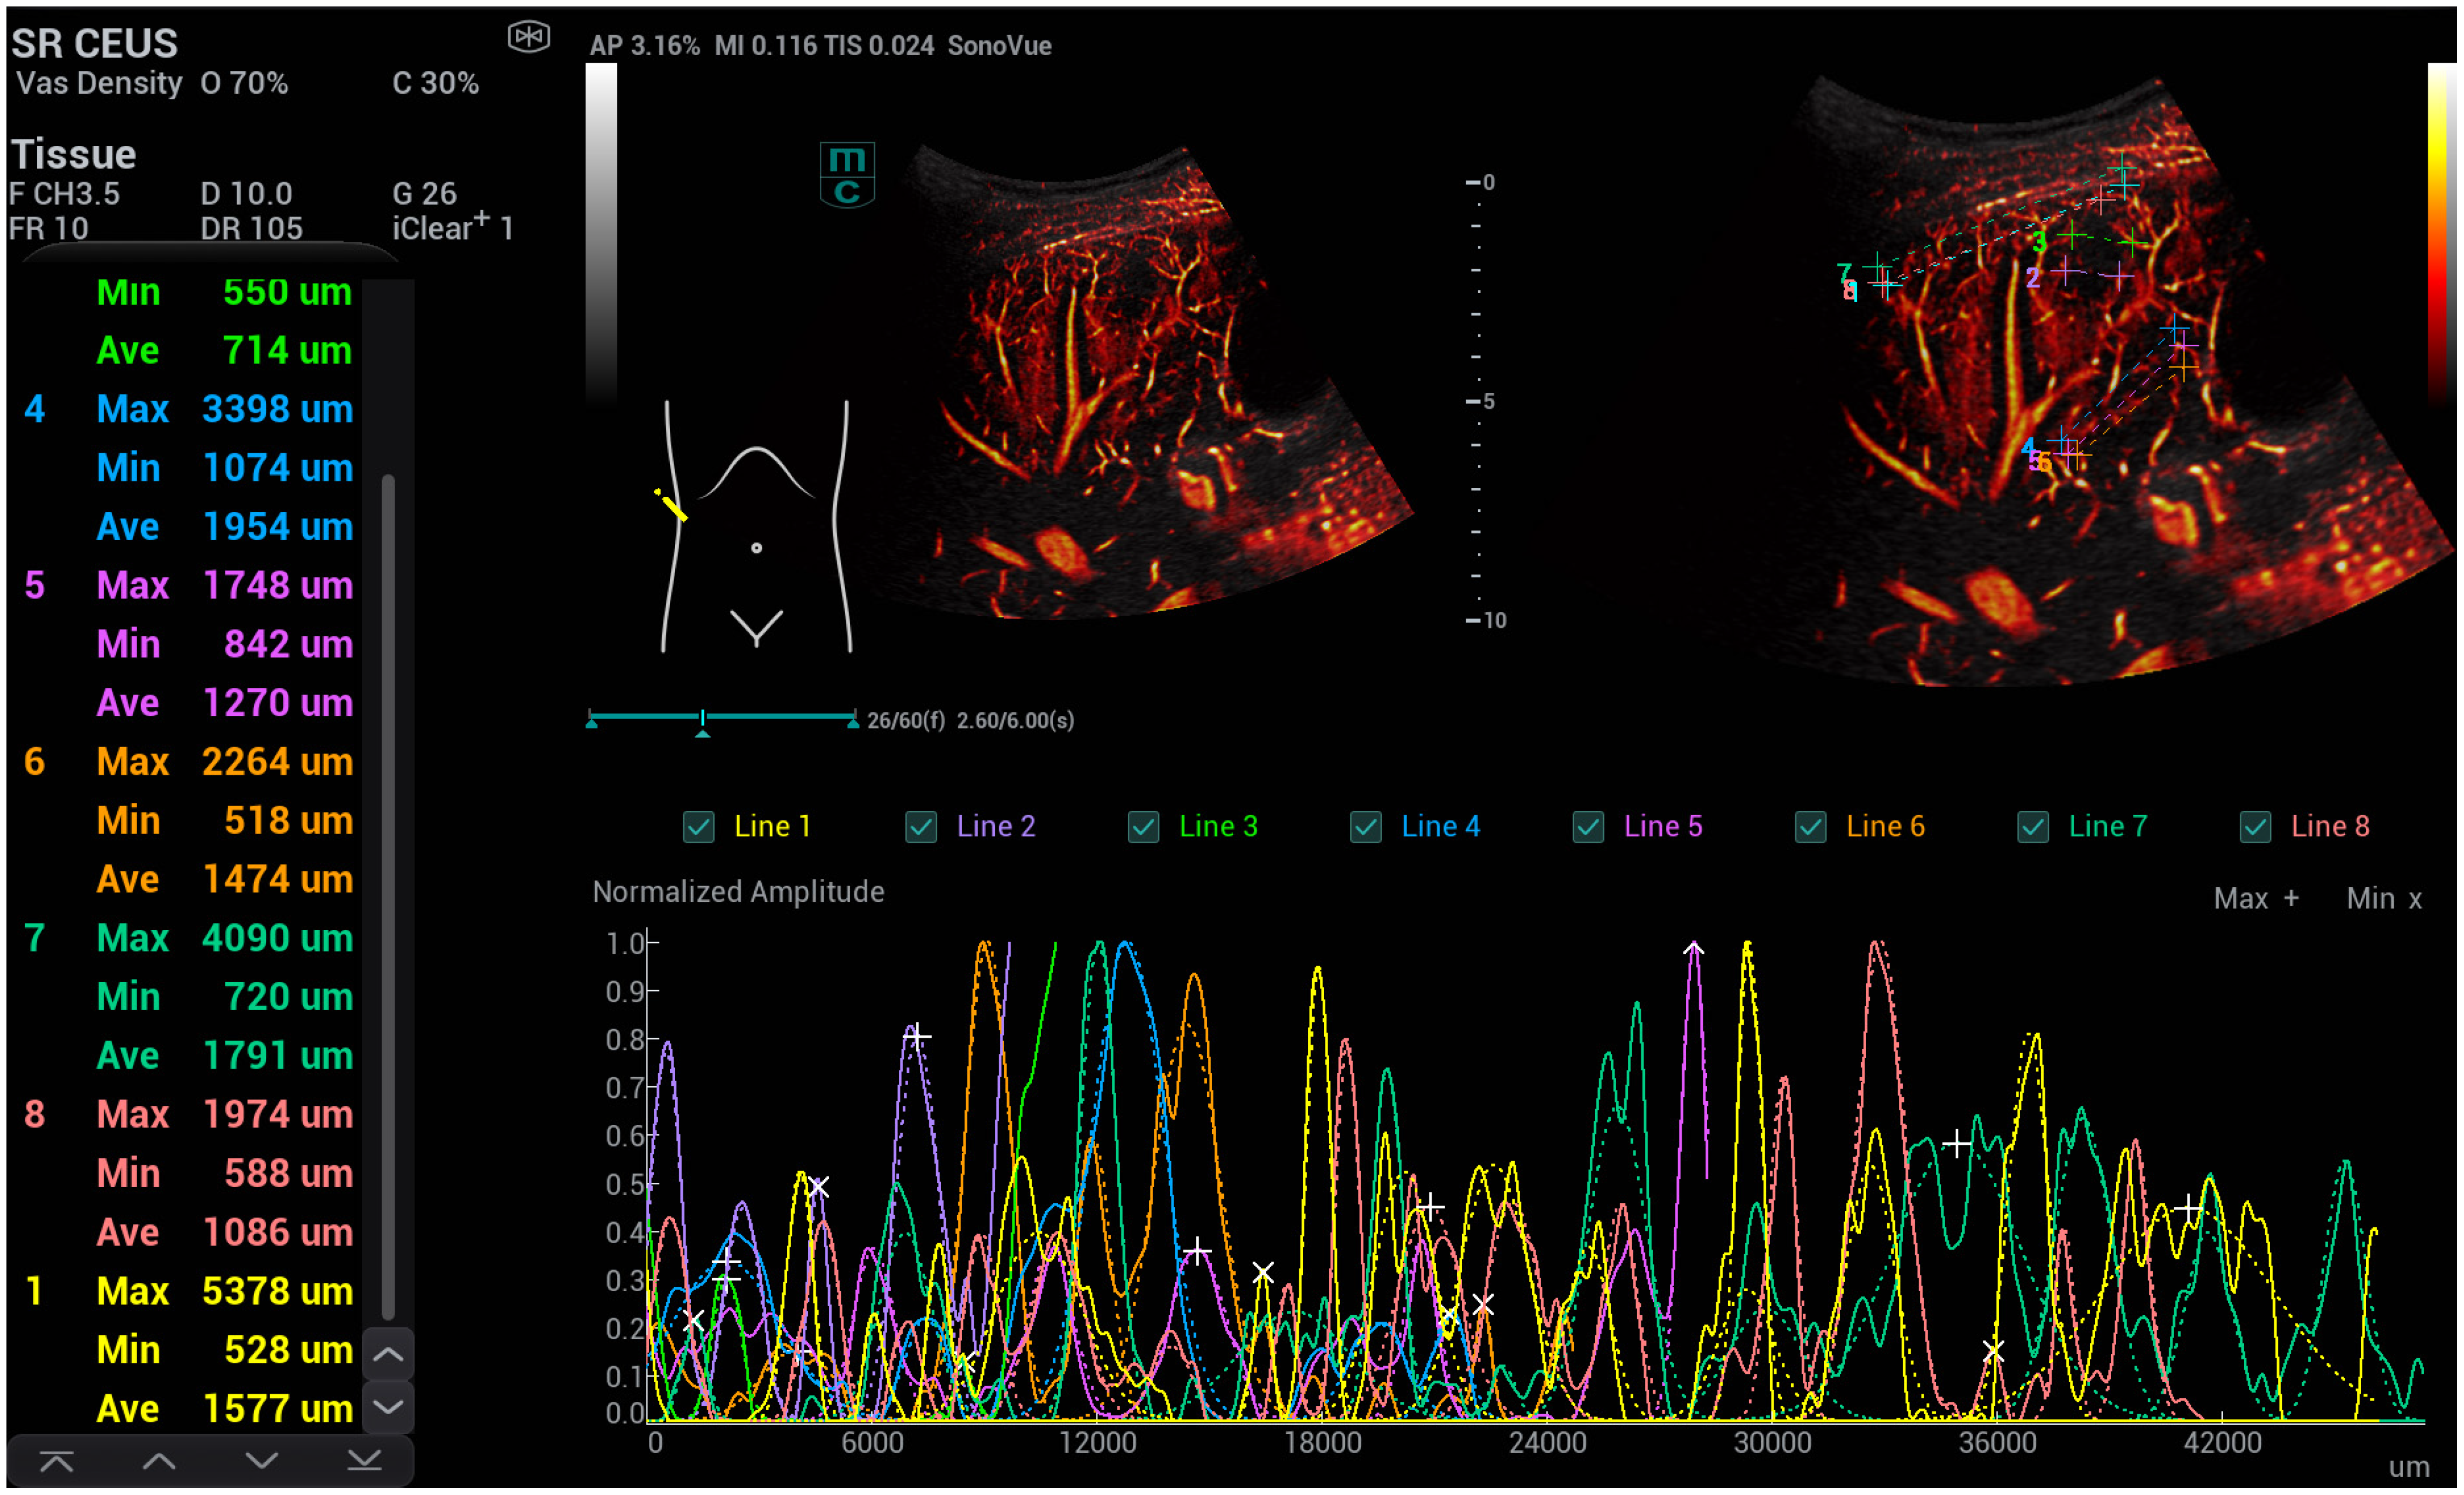

- Kaiser, U.; Vehling-Kaiser, U.; Kück, F.; Gilanschah, M.; Jung, F.; Jung, E.M. Super-Resolution contrast-enhanced ultrasound examination down to the microvasculature enables quantitative analysis of liver lesions: First Results. Life 2025, 15, 991. [Google Scholar] [CrossRef]